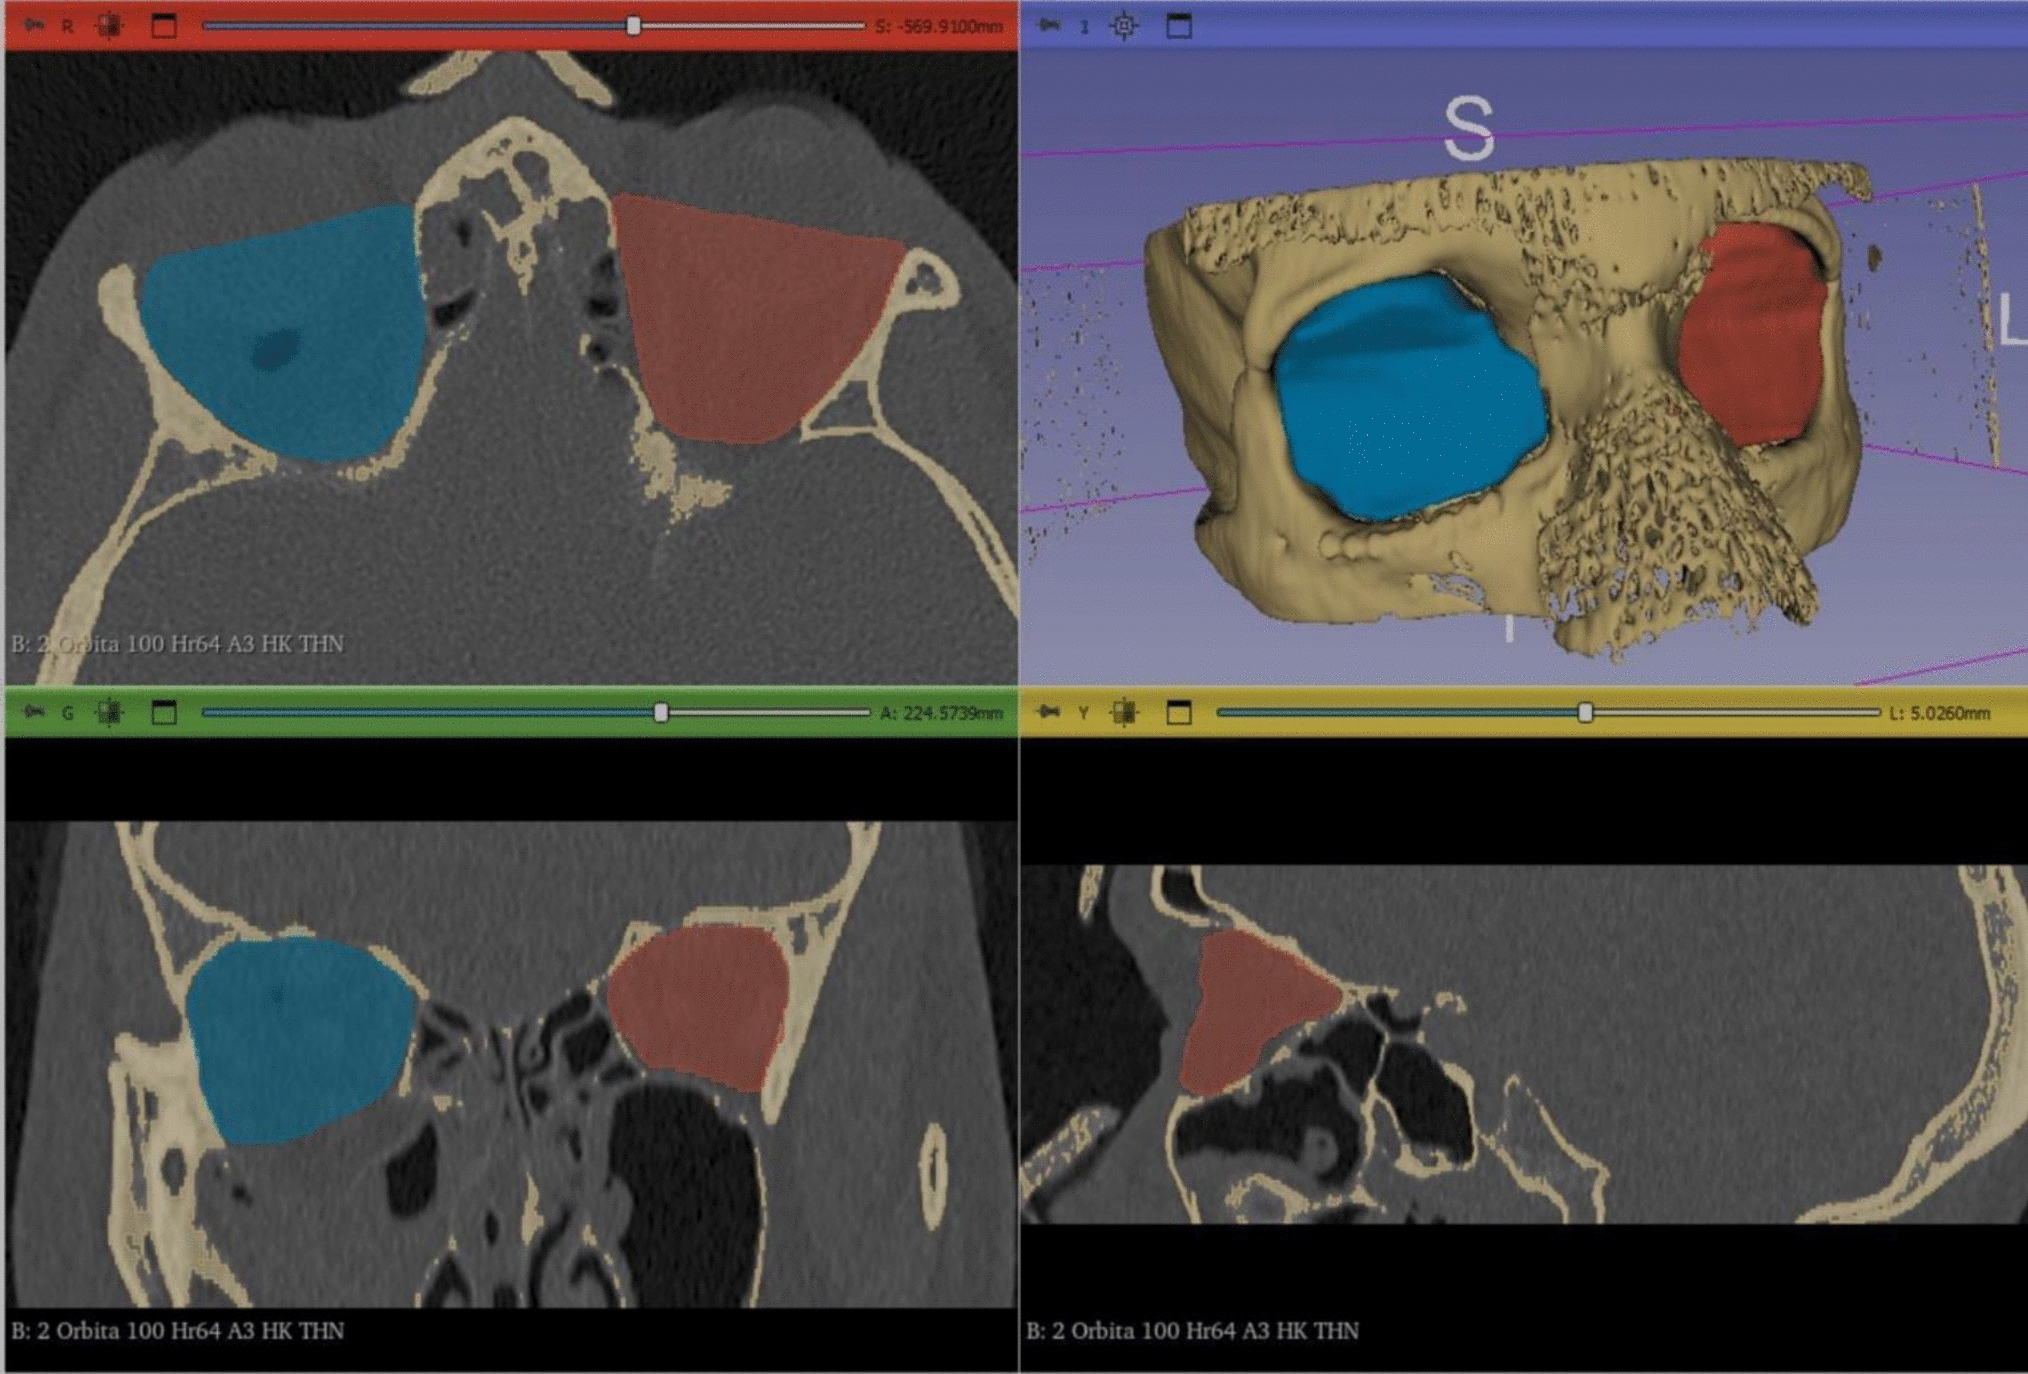

Fig. 3

Postoperative CT scan of the midface in axial (A), coronal (C), sagittal (D) and 3D reconstruction (B). Segmented volumes of the fractured and reconstructed (blue) and intact orbit (red) were generated using 3D-Slicer software

A total of 46 patients underwent preoperative 3D imaging (CT or CBCT scans) to assess fracture severity and location. Post-operative imaging was performed as clinically indicated to assess implant position and fracture reduction in the same manner. The scans were then reconstructed as axial, coronal, and sagittal slices and transferred to a three-dimensional imaging software program (3D Slicer ver. 5.6.1, https://www.slicer.org/) [9].

The following anatomical landmarks were used to segment the orbital volume as previously described [10]: the anterior orbital rim was defined as a straight line connecting the posterior surface of the lacrimal sulcus and the lateral orbital rim. The posterior margin was defined as the orbital apex excluding the optic canal. The herniated orbital contents were included in the measurement of the orbital volume. Volumetric analysis was performed by an independent third-party analyst (m3i GmbH – I.Z.) who was not involved in the study design or had contact with the study patients. Software calibration was utilized to further adjust the contrast in the CT images to ensure accurate marking of the anatomical landmarks, and a manual segmentation as per standardized measurement protocols was carried out [11]. Additionally, a specialist in each center, blindly verified the volumetric measurements to further increase the reliability and eliminate any potential bias. The resulting volume was calculated for each orbit in cm3 and a three-dimensional image was generated (Figs. 2 and 3).